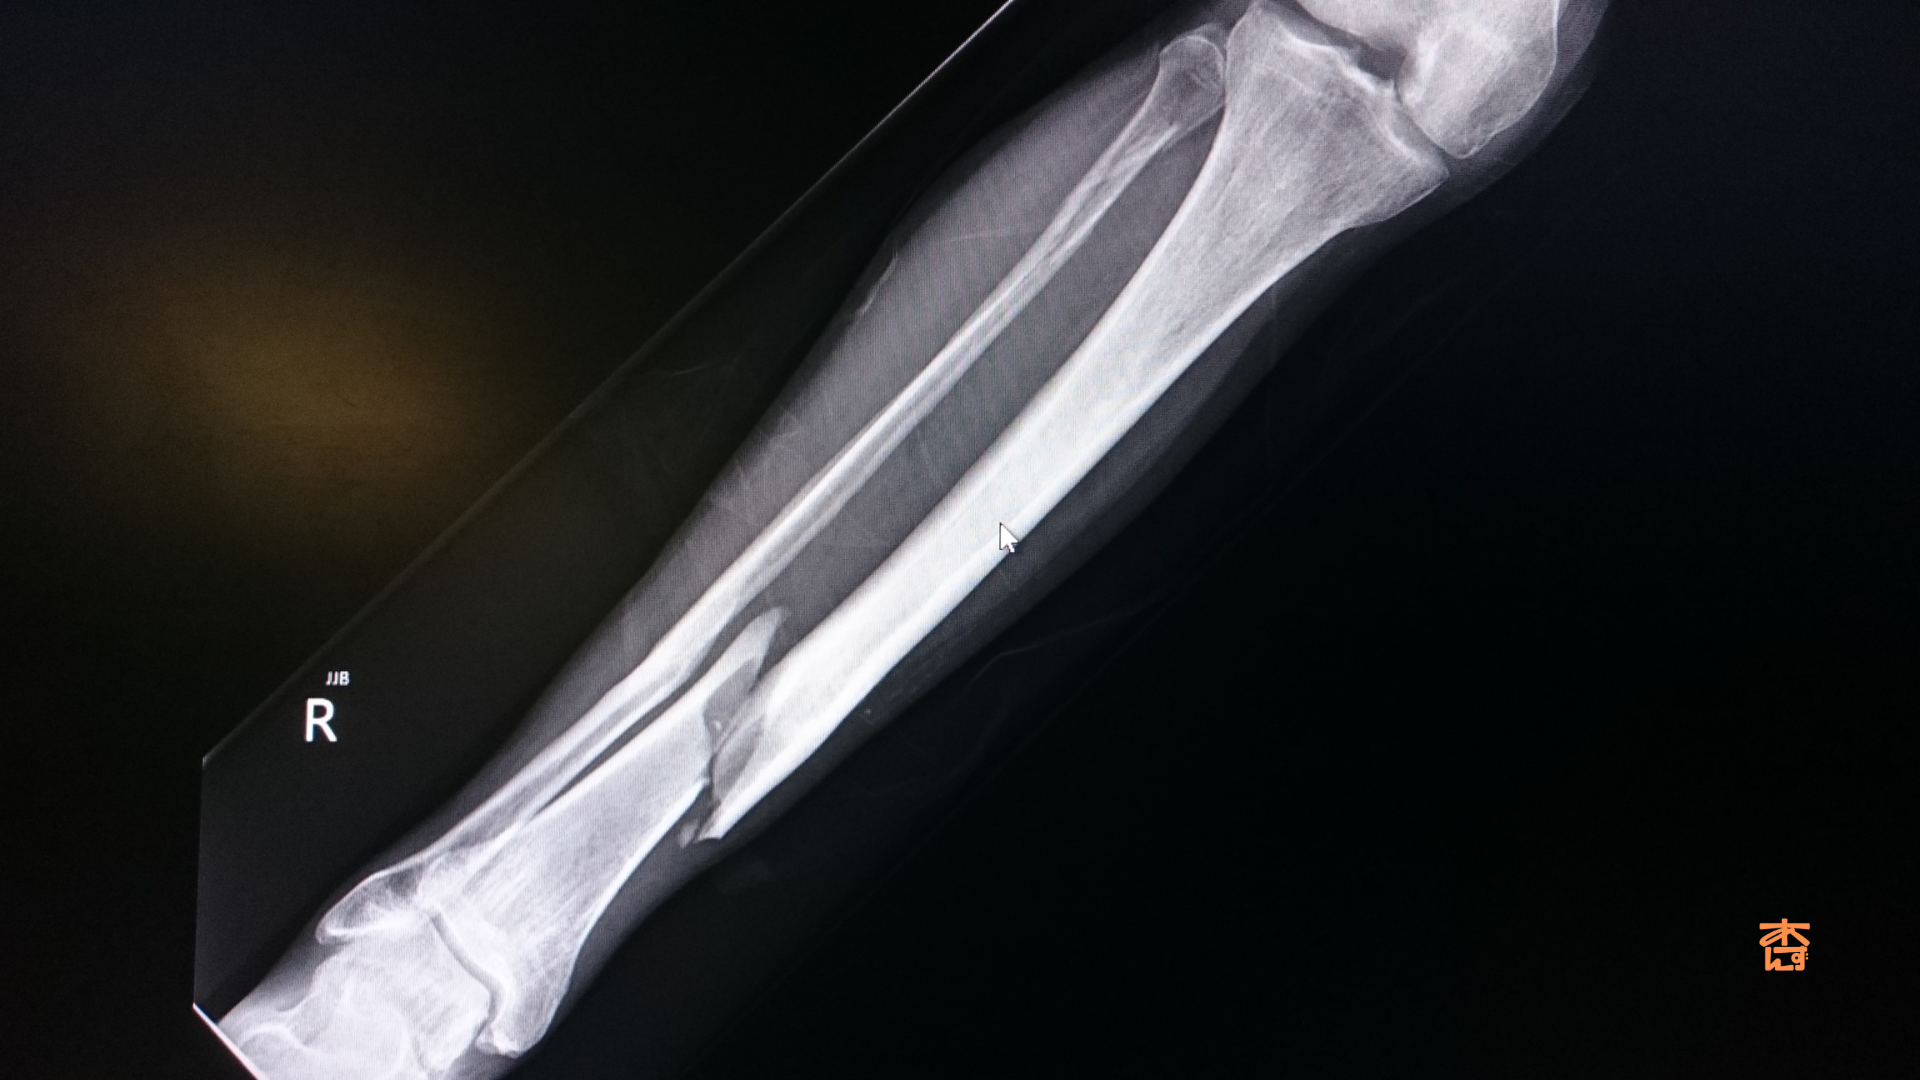

- 定期的な経過観察 レントゲンやMRIで骨の回復状態を確認します。